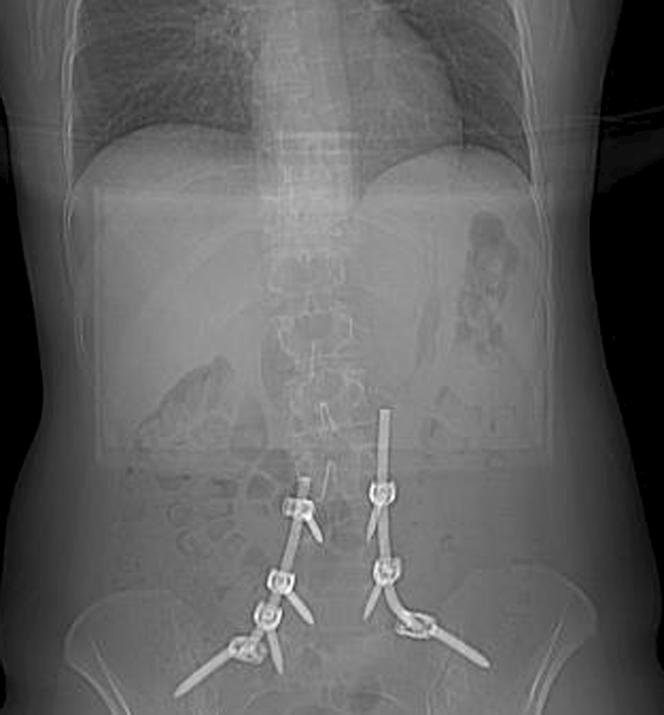

Ruszają mi się śruby w kręgosłupie